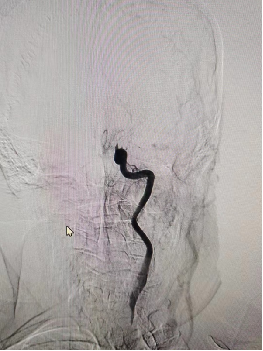

DSA:右侧颈内动脉正侧位

重要影像结论:右侧颈内动脉C6段狭窄约90%,长度约0.97cm。